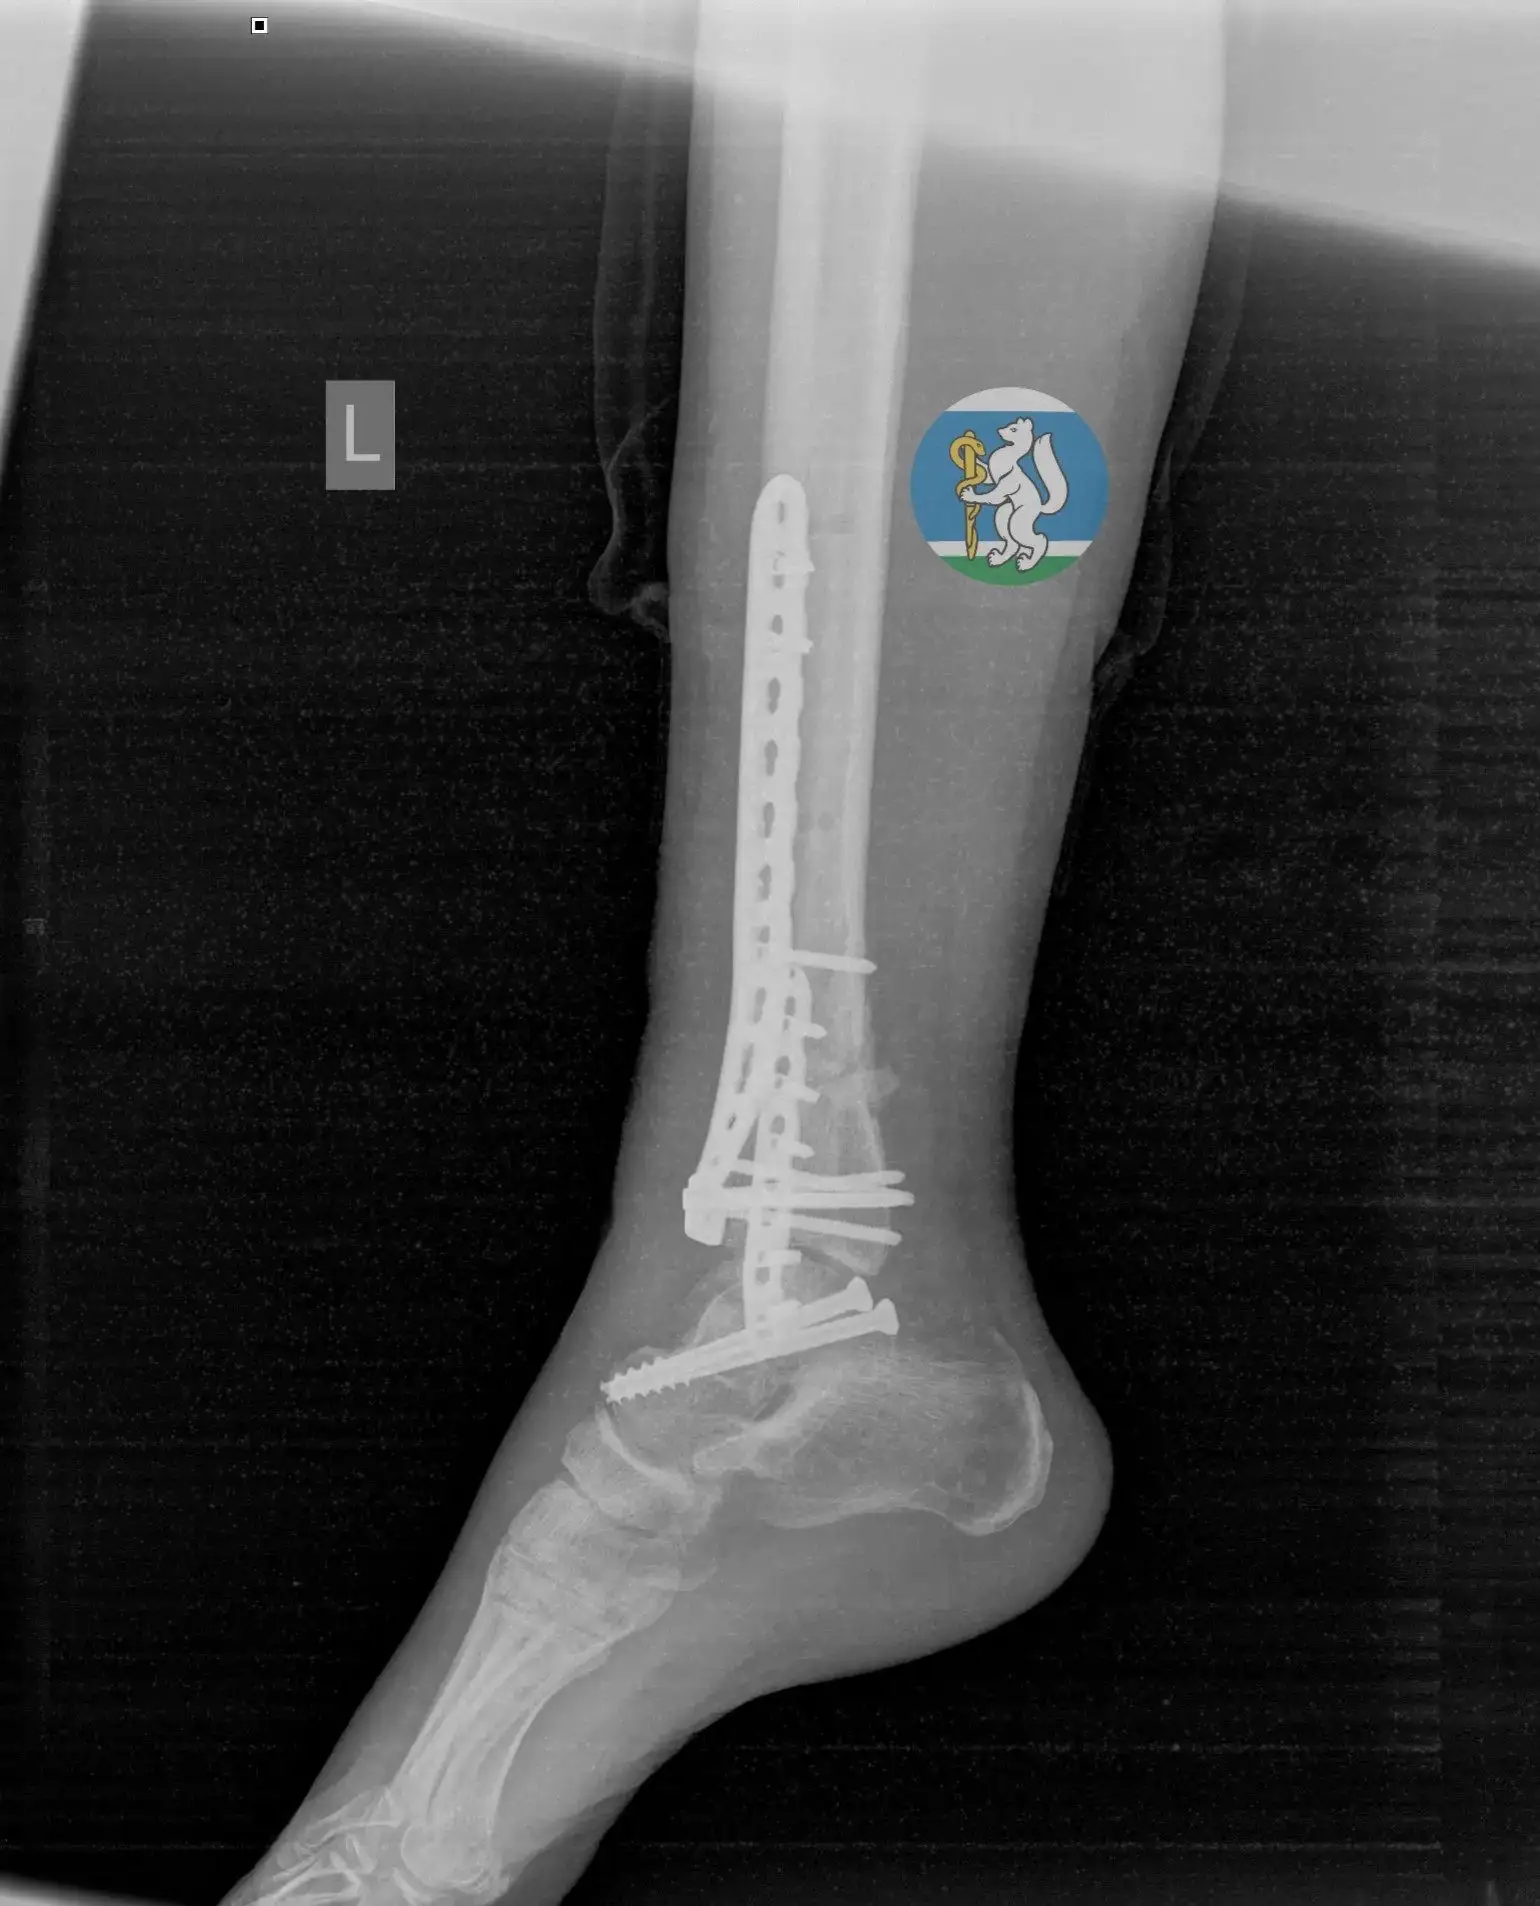

Татьяна Савинова: «Десять месяцев — и маленькая пациентка снова танцует»

Знаете, есть истории, которые напоминают: медицина — это не только диагнозы и протоколы. Это вера. Вера врачей в пациента. Вера родителей в чудо. И вера ребёнка в то, что боль не навсегда.

Вот Алиса. Обычная девочка: школа, друзья, мечты. И вдруг в 11 лет — тяжёлая травма позвоночника. Перелом.

Сегодня рада сообщить, что спустя 10 месяцев юная жительница Режа успешно прошла финальный этап долгого и сложного лечения — операцию по удалению импланта.

Благодаря слаженной работе команды врачей-травматологов и нейрохирургов Уральского института травматологии и ортопедии им. В.Д. Чаклина, невероятной силе духа юной пациентки и поддержке родителей жизнь девочки снова полна радости.

Несмотря на ограничения после операции и длительное ношение шейного корсета, который разрешили снять только в феврале 2026 года после полного сращения позвонков, Алиса продолжила заниматься в хореографической школе, чтобы быть в форме и не отстать от своих сверстниц. Родители поддерживали дочь на каждом этапе, и эта помощь стала неотъемлемой частью пути к выздоровлению.

Недавняя операция по удалению металлоконструкций — завершающий аккорд в этой непростой истории. В знак признательности Алиса приготовила творческую композицию для своего лечащего врача, нейрохирурга Антона Пьянкова. Сувенир стал для доктора сюрпризом и лучшей наградой за труд.